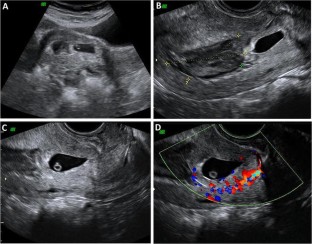

Cesarean scar pregnancy (CSP) is a rare kind of ectopic pregnancy implanted in the previous cesarean scar and has an increasing incidence over the past 30 years. As the suspicion is low, the diagnosis may be delayed or misinterpreted in ultrasound, leading to treatment strategies that might end up in uterine rupture or hysterectomy. The objective here is to review the ultrasound findings in CSP with varied presentations. Transabdominal and transvaginal sonography combined with color Doppler is a reliable tool for the diagnosis of CSP. When the gestational sac is seen in lower part of the uterine cavity, differentiation between threatened miscarriage, cervical pregnancy and CSP could be difficult. Not all cases of CSP present with typical ultrasound findings and a high index of suspicion is needed for diagnosis in these cases. An attempted curettage or MTP pill taken in an undiagnosed CSP often alters the typical findings. The possibility of CSP should also be considered in cases presenting with abnormal uterine bleeding and have a prior history of cesarean section. With lack of awareness about this condition, the diagnosis can often be missed either with MRI or in ultrasound. Correct interpretation and timely diagnosis save the mother from life-threatening complications and also preserves future fertility.

Fig. 3